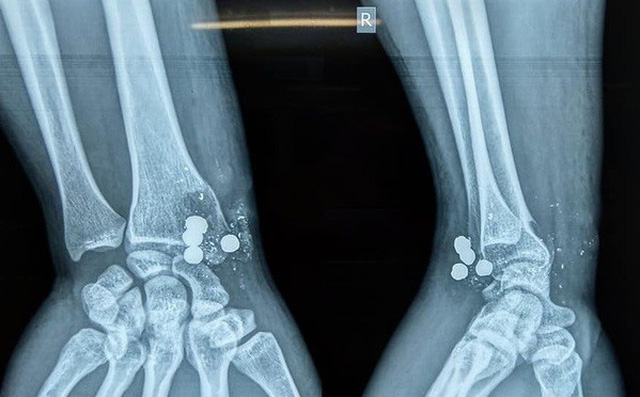

Ngày 9/5, thông tin từ Bệnh viện Đại học Y khoa Vinh (Nghệ An) cho biết, Bệnh viện đã phẫu thuật thành công cho một bệnh nhân bị vỡ đầu dưới xương quay phải do đạn bắn.

Trước đó, anh L.V.T. (27 tuổi, trú tại xã Lạng Khê, Con Cuông, Nghệ An) đến nhà bạn chơi. Tại đây, anh T. thấy khẩu súng kíp gác trên mái nhà nên kéo xuống xem chơi. Bất ngờ súng nổ, 5 viên đạn bắn thẳng ở cự ly gần vào cổ tay phải của thanh niên này.

Thăm khám và chụp chiếu tại bệnh viện Đại học Y khoa Vinh, bác sĩ phát hiện anh T. bị vỡ đầu dưới xương quay, tổn thương cung động mạch gan tay sâu, không tổn thương gân gấp duỗi và các dây thần kinh.

Trong cổ tay anh T. còn 4 mảnh bạn lớn bằng chì và nhiều mảnh kim loại nhỏ khác. Một viên lớn đã xuyên từ trước ra sau.

Ngay lập tức, các bác sĩ phẫu thuật lấy hết các mảnh đạn và chất độc trong đạn, cắt lọc sạch vết thương, ghép lại mảnh xương vỡ, thắt động mạch bị đứt do quá thời gian có thể nối. Hiện, sức khỏe anh T. dần hồi phục.